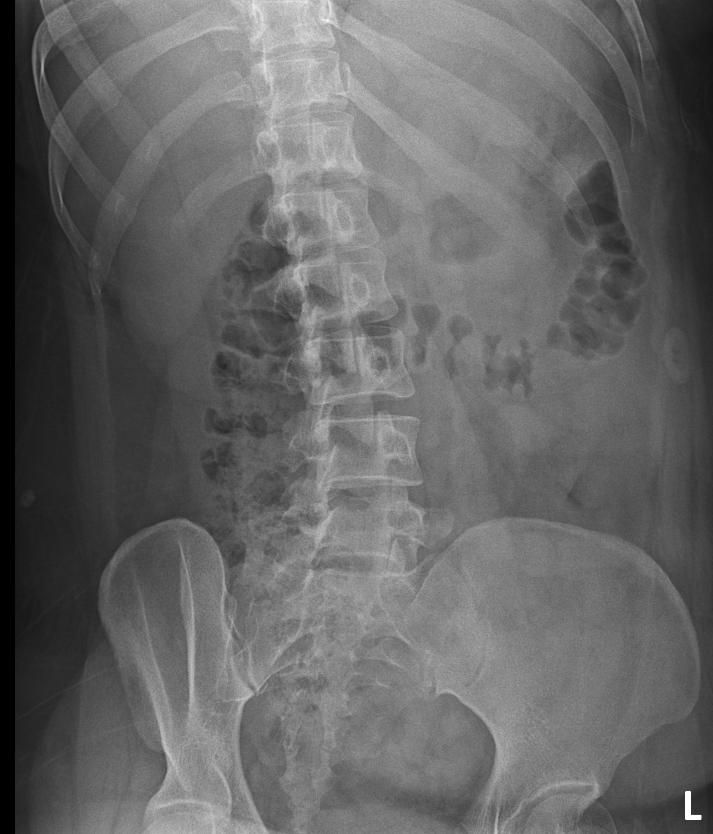

척추분리증인가요??(엑스레이 있어요)

한 병원에서는 척추분리증이라고 하고 한 병원에서는 척추분리증이 아니라고 해서요. 혹시 아래 사진에서 척추분리증 소견이 보이는 사진이 있나요??

여기까지가 a병원에서 찍은 사진이고 아래가 b병원에서 찍은 사진이에요!

• 1번 째 사진

• 2번 째 사진

• 3번 째 사진

척추분리증 맞습니다.

A병원 세번째 사진의 아래 부위에 척추분리증이 있는게 맞습니다.

B병원 사진에서는 비교적 흐리게 보이지만 잘 보면 B병원 엑스레이에서도 같은 부위에 분리증을 확인할 수 있습니다.